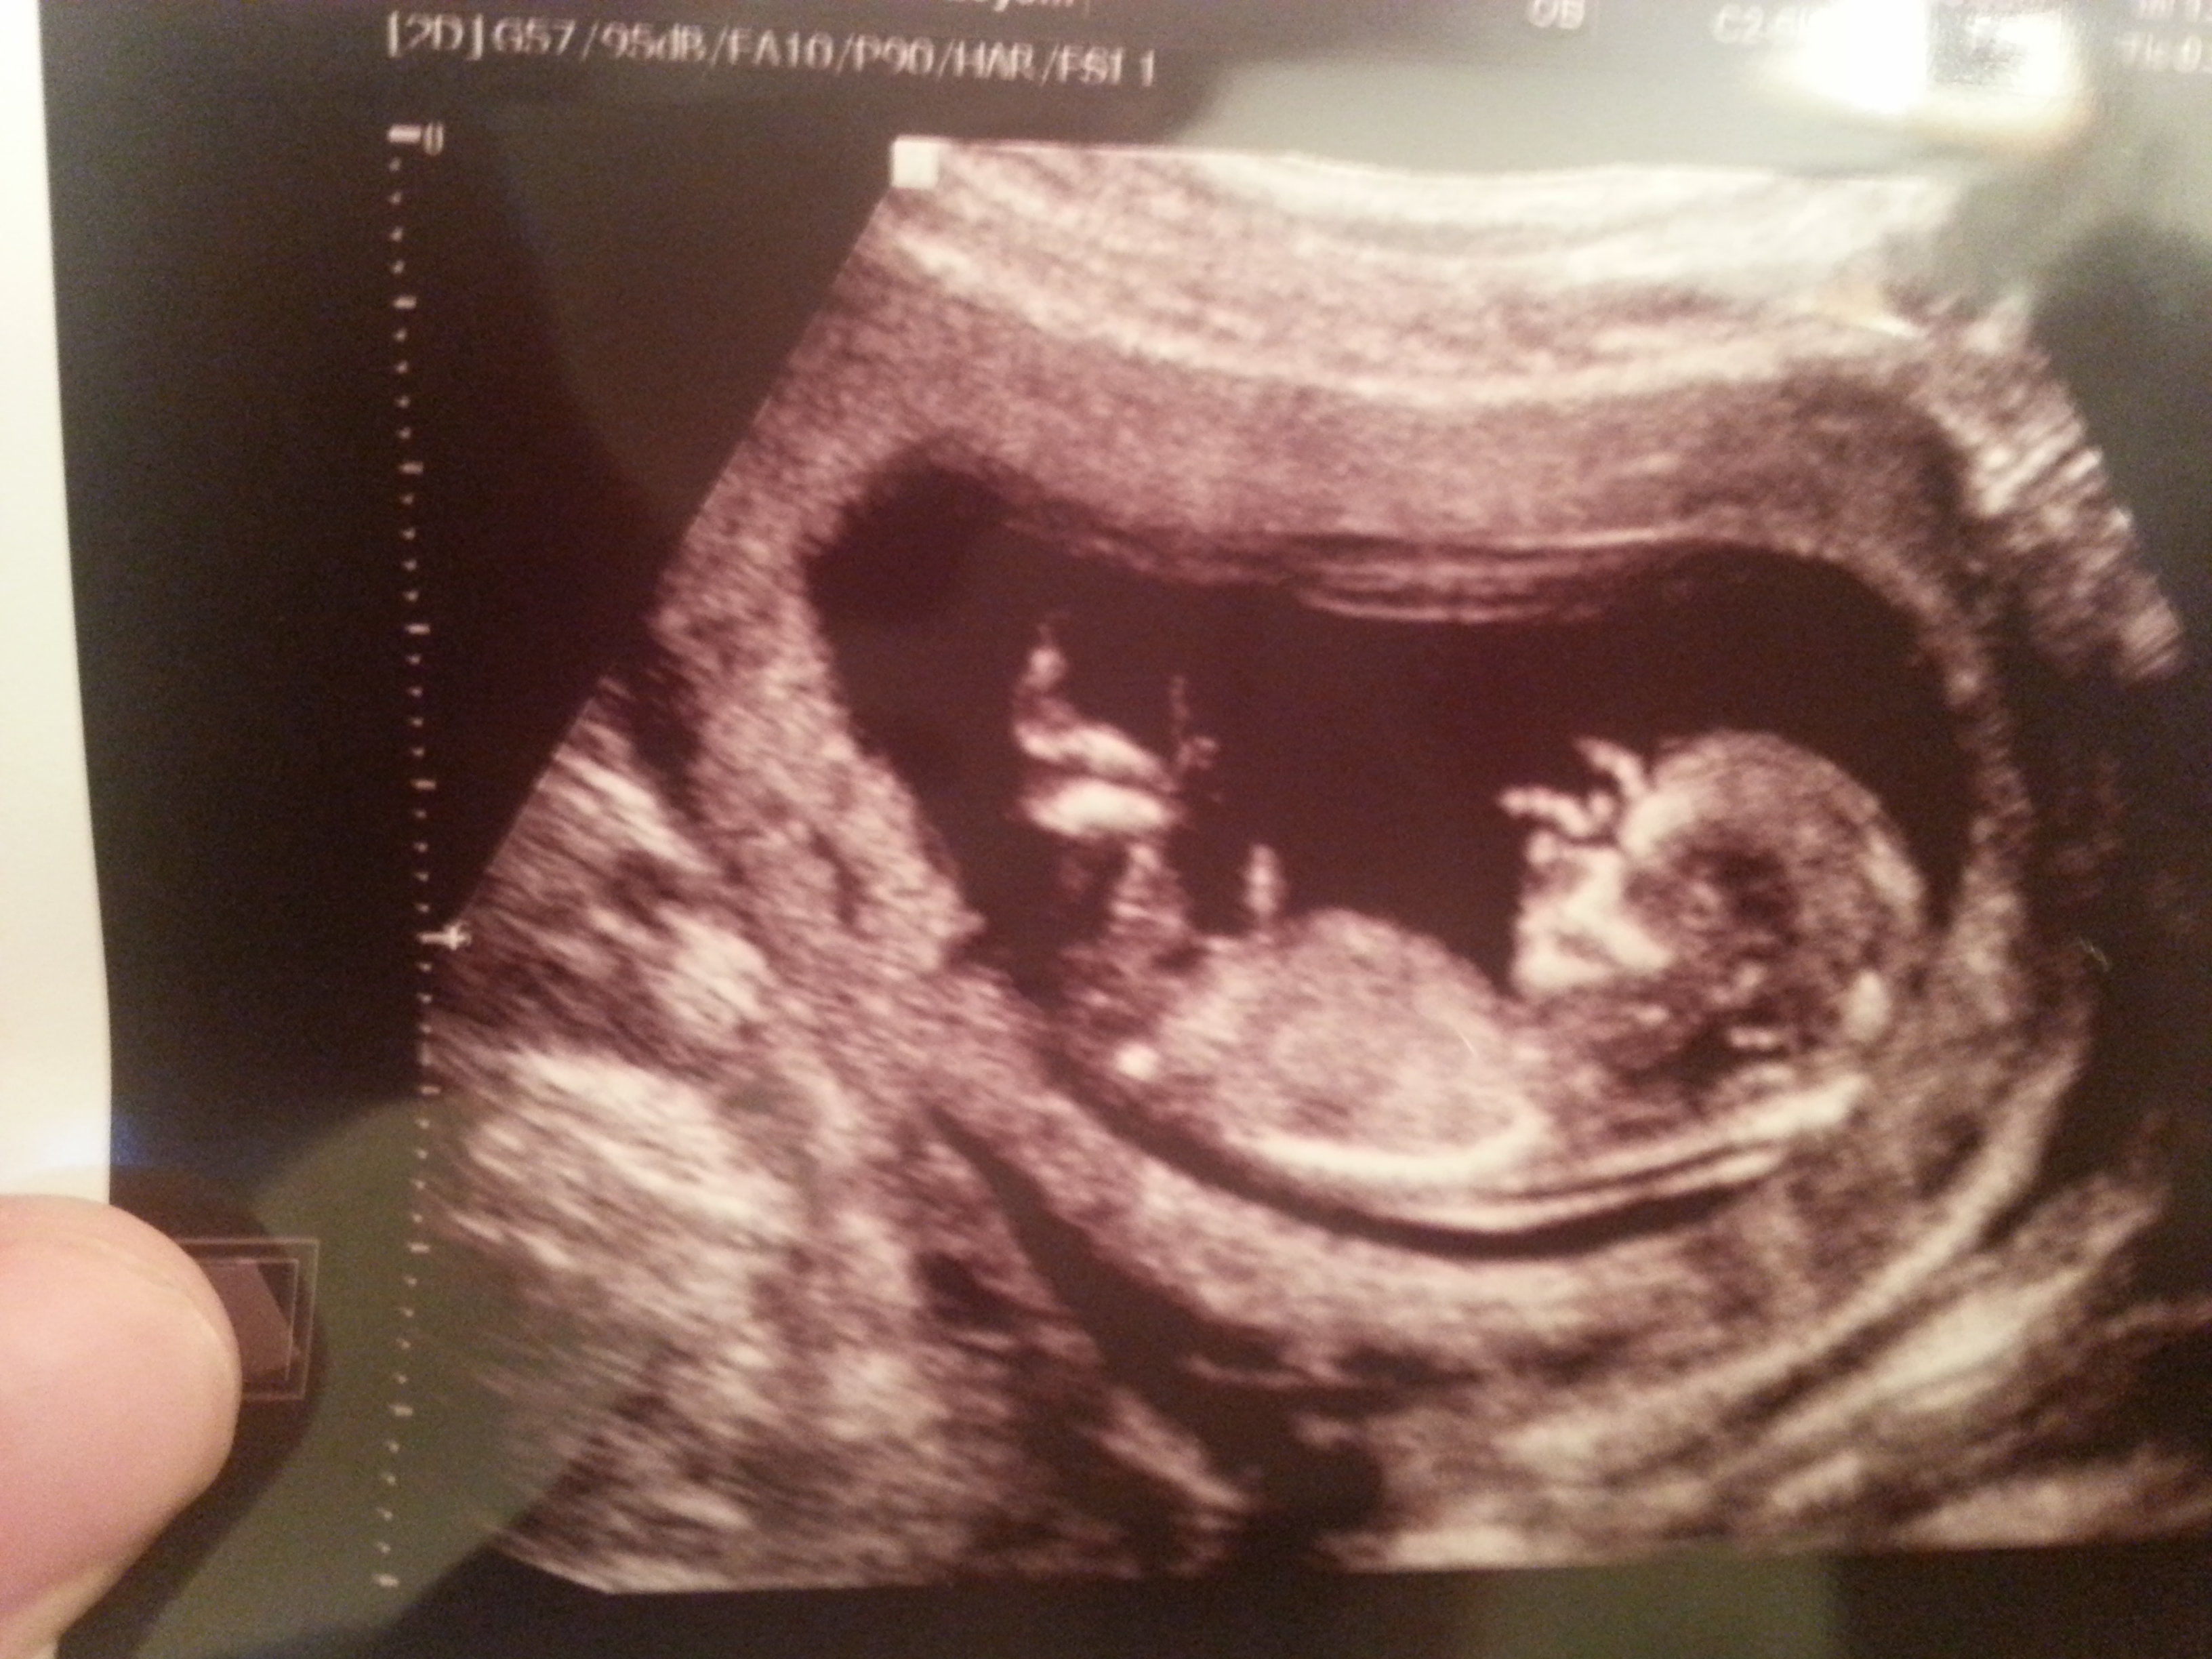

I am not sure. How far along are you. It's rounded which is promising for a boy but it is very stubby and doesn't scream penis to me. The legs are blocking the nub.

Babe looks young. But it's possible to see some potential for a boy. We saw pretty district boy stuff at 13 weeks (w/ #1) which I now know I shouldn't have totally believed...but it didn't matter, he was a boy. There is hope :)